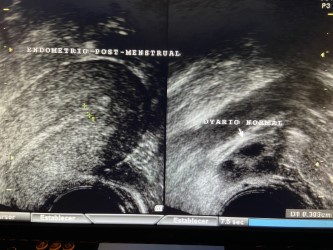

Una vez que el folículo maduro se ha roto -ha estallado- y se ha expulsado el óvulo que contenía (ovulación) la capsula del folículo adquiere un aspecto rugoso, grueso e irregular al que llamamos “cuerpo lúteo”. En su interior, frecuentemente, se produce un acúmulo de sangre por lo que también se le conoce como cuerpo lúteo hemorrágico.

Además de estrógenos, este cuerpo lúteo empieza a segregar una hormona llamada Progesterona; la cual, es la causante de que el endometrio- que antes de la ovulación era proliferativo y con sus tres capas bien definidas- se transforme en un endometrio grueso, espeso e irregular. Se le conoce como “endometrio secretor”.

La producción de estrógenos y sobre todo de Progesterona, por parte del cuerpo lúteo, permanece durante unos 14 días, al cabo de los cuales, si no ha habido embarazo, bajan bruscamente los niveles de estas hormonas y aparece la menstruación. Se desprende y expulsa el endometrio. Empieza así un nuevo ciclo menstrual.

Sumando los 14 días que suele durar la fase folicular o proliferativa a los otros 14 que dura la fase lútea, luteínica o secretora, nos dan los 28 días que suele durar el ciclo menstrual.